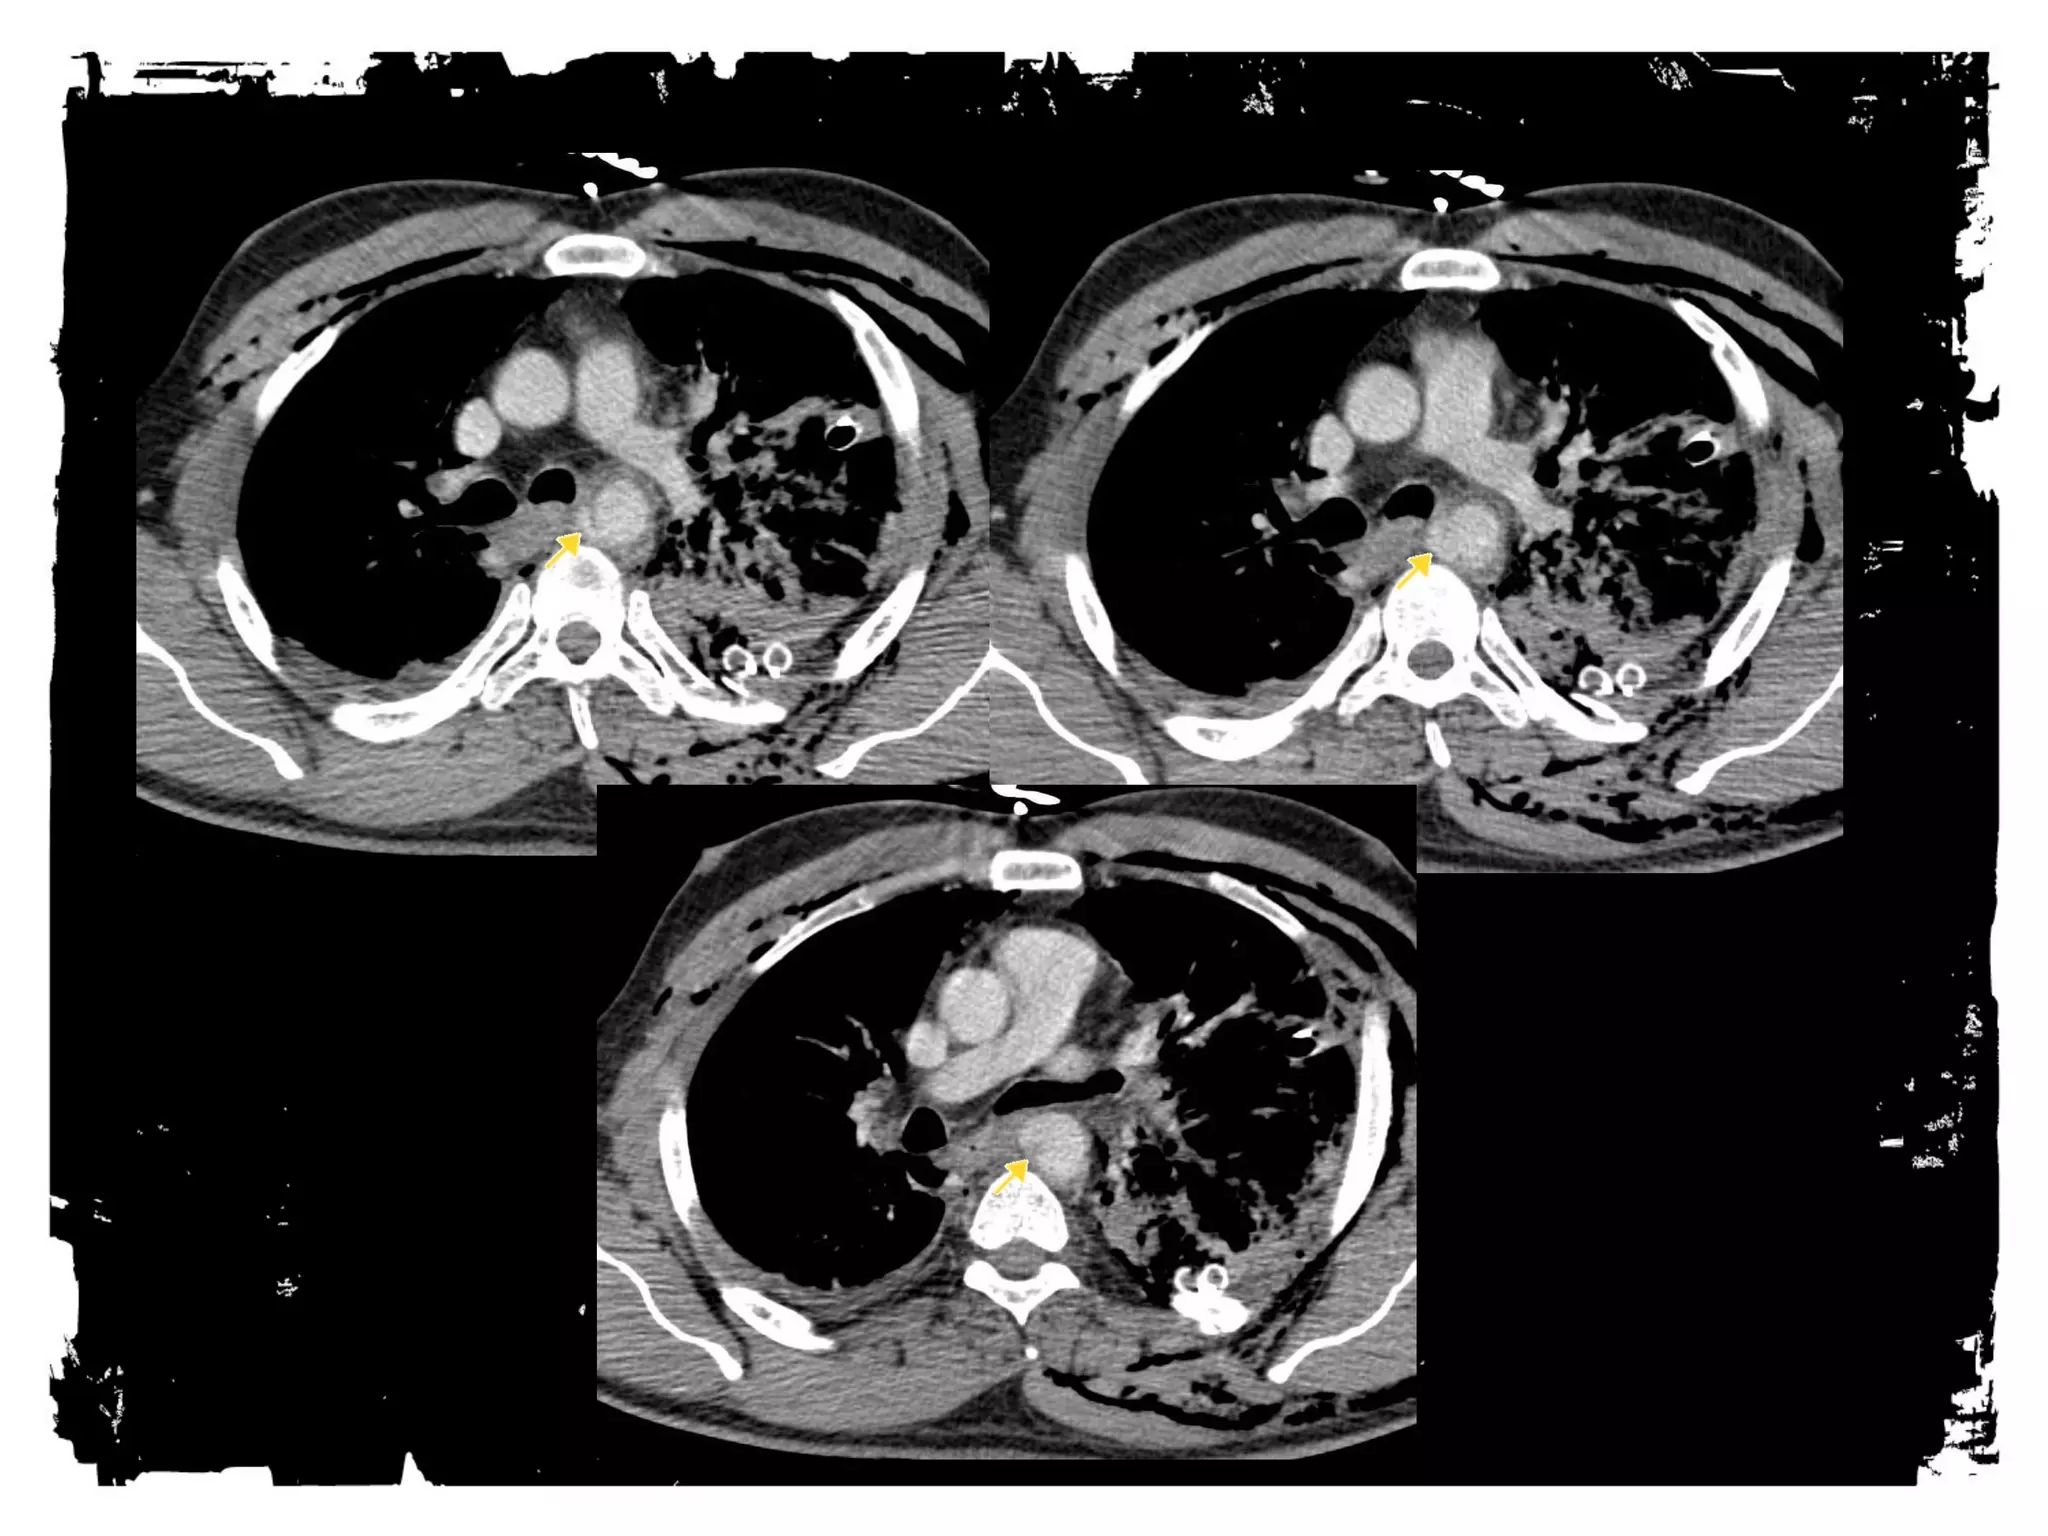

Traumatic aortic rupture

HEMOTHORAX

• Venous or arterial bleeding

• 60% controlled by chest tube,

40% need operative

management

• Can miss hundreds of cc’s on

supine film

• Can be tension